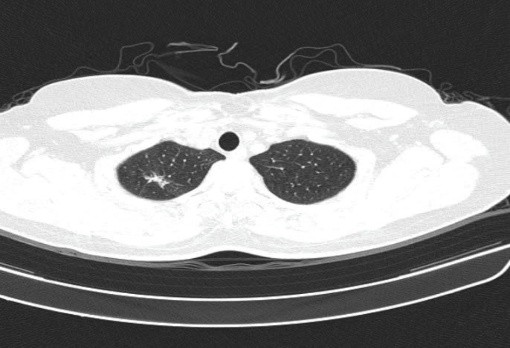

– Cắt lớp vi tính lồng ngực: đám xẹp đông đặc đỉnh phổi phải kích thước 11mm; nhu mô phổi rải rác nốt đặc 5-10mm. Trung thất cân đối có vài hạch 10mm

Hình 6: Hình ảnh cắt lớp vi tính ngực có tiêm: đám xẹp đông đặc đỉnh phổi phải kích thước 11mm (mũi tên xanh nước biển)

Hình 7: Hình ảnh cắt lớp vi tính ngực có tiêm: Trung thất cân đối có vài hạch 10mm (mũi tên vàng). Hạch trung thất giảm kích thước rất nhiều chỉ sau 03 chu kỳ.